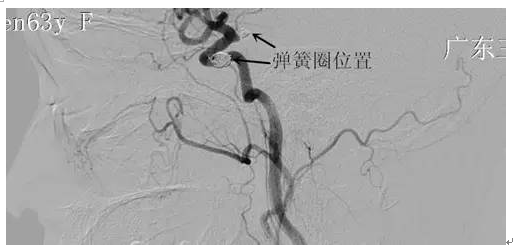

周阿姨,63岁,突发性头痛20小时,就诊当地医院CT示:蛛网膜下腔出血。为求进一步治疗,来我院就诊。入院后完善相关检查,检查提示:右侧后交通动脉瘤,左侧颈内动脉动脉瘤,行介入栓塞治疗去除动脉瘤。病人经系统治疗后颅内血肿完全吸收,头痛缓解,康复出院。